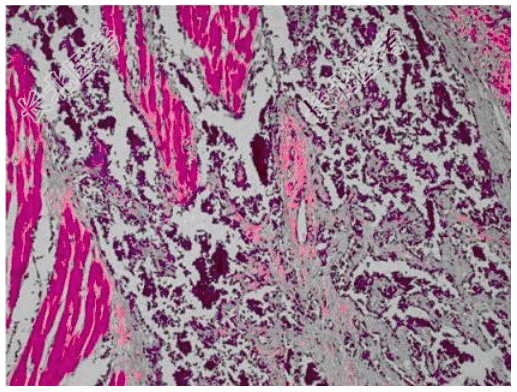

- [材料题] 患者男,18岁,会阴肿块,影像学表现如图所示。行穿刺活检,镜下形态如图所示。

- 简答题1、首先考虑的诊断是?

- 简答题2、该肿瘤的染色体异常表现为?

- 简答题3、该肿瘤好发于?